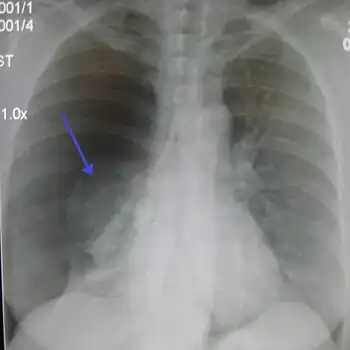

| A large right-sided spontaneous pneumothorax (left in the image). An arrow indicates the edge of the collapsed lung | |